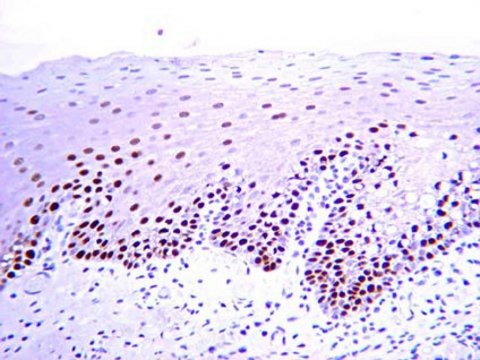

Immunohistochemistry: 1:20-1:200. Recommended for paraffin embedded tissue sections only. May be used on material fixed in a wide range of fixatives including formalin (buffered and unbuffered), methacarn and Bouin′s reagent. The time of fixation can markedly affect the intensity of PCNA immunoreactivity. Staining is reduced (and may be abolished) if sections are baked onto glass slides. Air-drying overnight on poly-L-lysine coated slides is recommended. 60 minute incubation at 25°C with standard ABC technique is recommended.

Clone PC10 recognizes PCNA from all vertebrate and insect species tested and has been used to identify transformed cells (Kurki, 1988), proliferating cells in solid tumors (Smetana, 1983), and blast cells in leukemia patients (Takasaki, 1984). Immunohistochemistry with clone PC10 has been used to study the expression of PCNA in paraffin sections of normal tissues and lymphoid neoplasms (Hall, 1990). In proliferating cells, PCNA staining pattern is predominantly nuclear. By western blot, the antibody detects a polypeptide migrating at 36 kDa with an isoelectric point of 4.8.